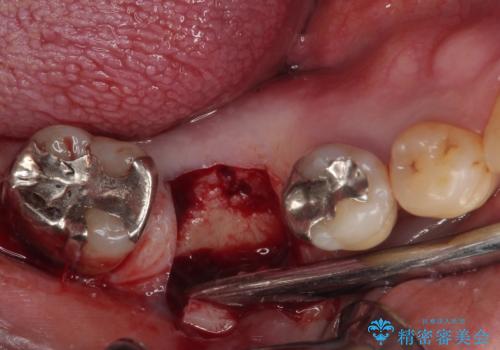

- 奥歯を抜歯してから放置しているとのことで来院された患者様です。

歯が割れて抜歯になってしまったとのことで、咬合力に抵抗できるよう、インプラントによる補綴治療を行うこととしました。

むし歯の放置期間と抜歯してからの放置期間が長く、咬み合わせる上顎の歯がやや伸び出している状態でした。

上顎の部分矯正や対合歯の補綴治療も提案しましたが、今回は欠損部のみの治療を行いました。